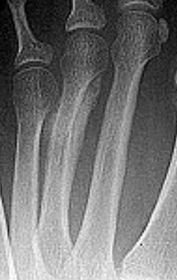

Describe the alignment of metatarsal 2 | There is no angulation nor displacement of the distal segment relative to the proximal segment. |

Describe the alignment of metatarsal 3 | The distal segment is displaced laterally (50% apposition) and angulated medially. |

Describe the alignment of metatarsal 4 | The distal segment is displaced laterally (75% apposition) but there is no apparent angulation. |

Describe the tubulation of the metatarsals | Metatarsals are overtubulated - decreased girth. |

Describe the tubulation of the metatarsals | Metatarsals are undertubulated - increased girth. |